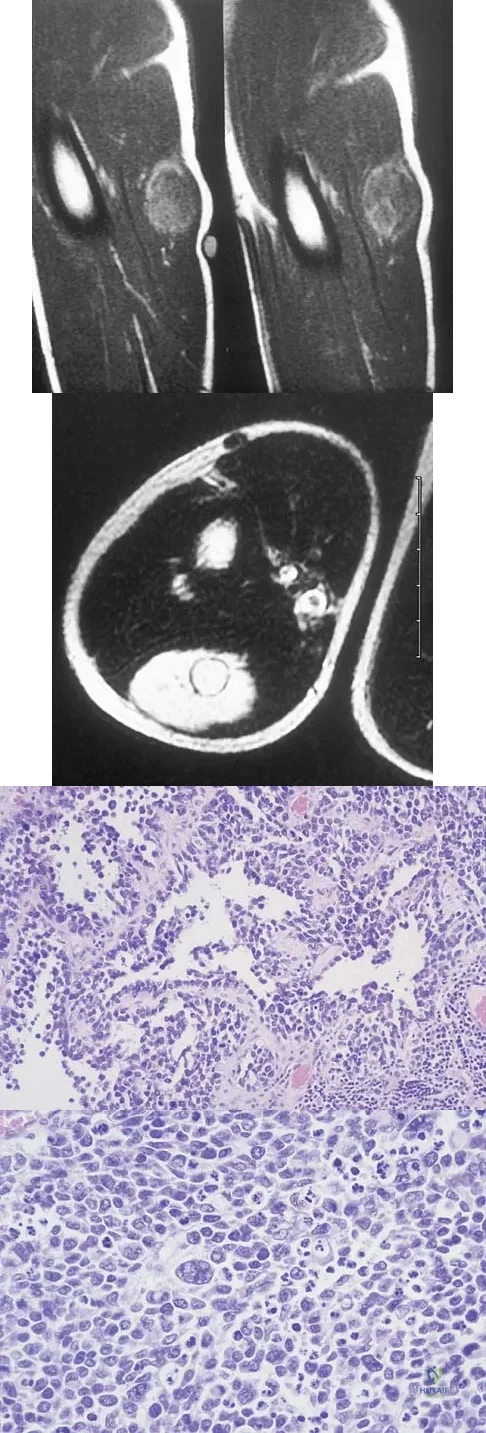

A 13-year-old boy has had a painless mass in the arm for the past 2 months. An MRI scan and biopsy specimens are shown in Figures 46a through 46c. What is the most likely diagnosis?

Explanation

A 14-year-old boy has an asymptomatic mass on the right arm. MRI scans and biopsy specimens are shown in Figures 51a through 51d. Immunostaining is positive for desmin. Additional staging studies should include

Explanation